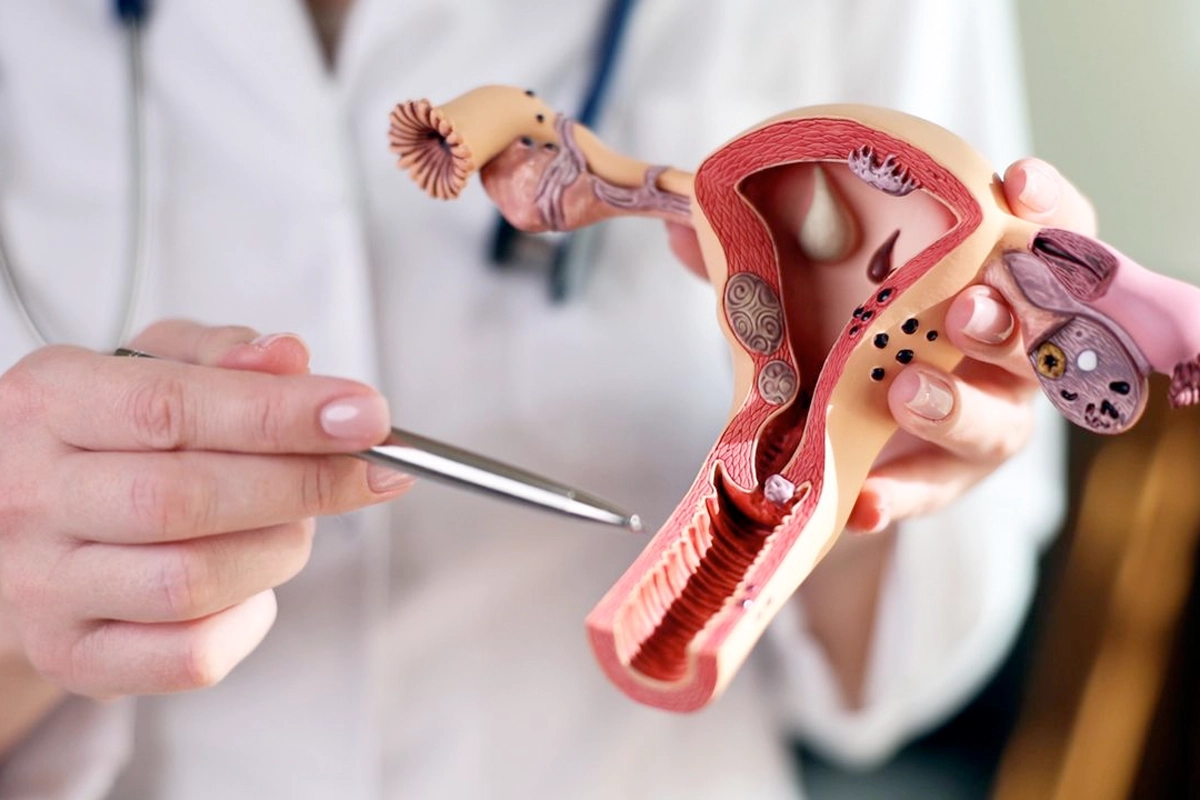

The team manages well-woman exams, birth control, and Pap smears. They offer high-quality care for complex health issues as well, such as abnormal bleeding, ovarian cysts, and endometriosis. Patients can also take advantage of the family planning and infertility services available at the practice.

Careful diagnosis and treatment planning for ovarian cysts and related symptoms.

Supportive, individualized care to help manage pain, symptoms, and long-term reproductive health.